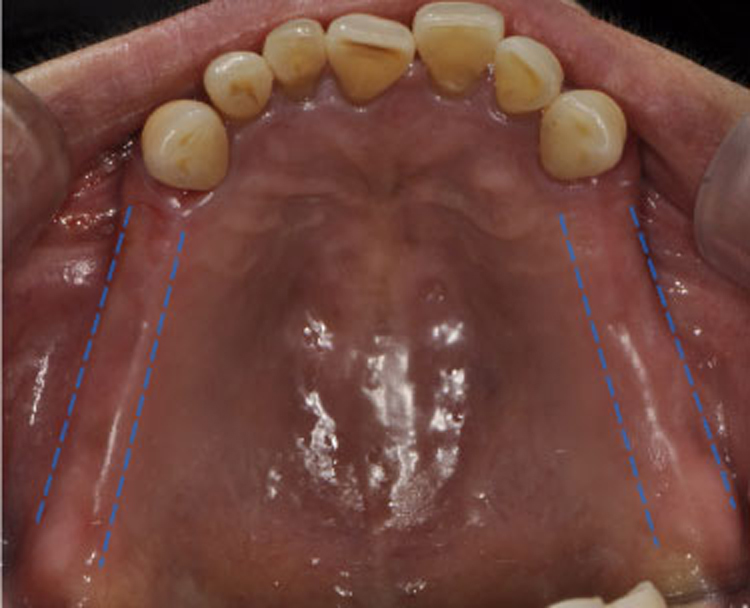

치료후 : 2018-09-27